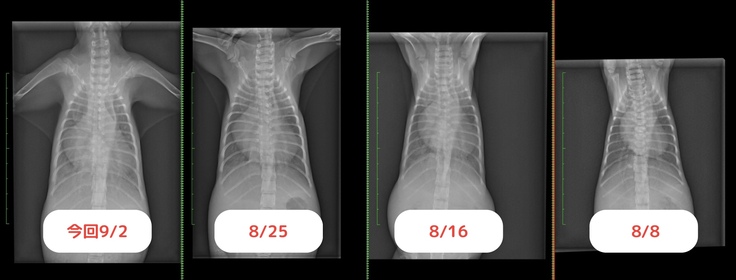

8/25 経過を診てもらうために通院。

調子が良いので肺の水が無くなって、体も少し大きくなり心臓が小さくなったかと思いましたが、すごく良い!という状態ではないみたいです…。

まだ肺に水はあり、心臓も大きいままです。

レントゲン写真を見せてもらいましたが、体が大きくなって、心臓もかなり大きくなっていました。肺も相変わらず、真っ白に…

↓1番左が今回のレントゲン